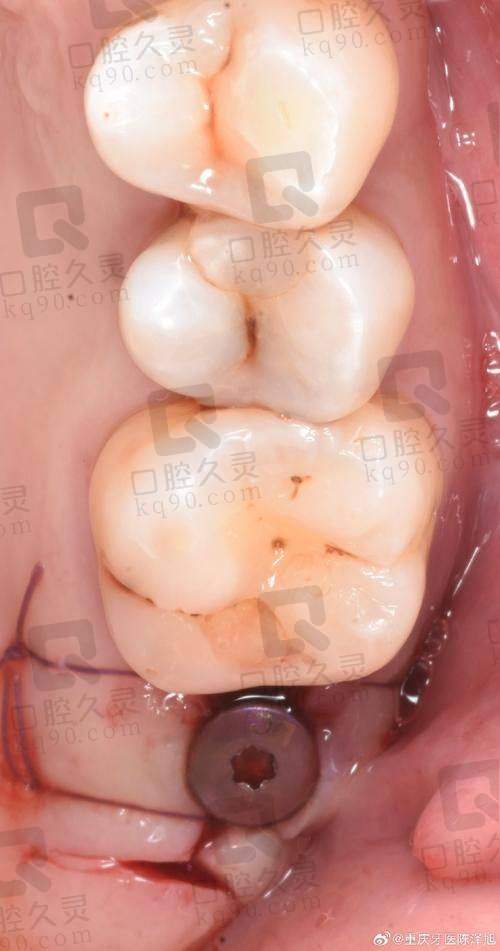

根据我的检查结果,医生为我制定了个性化的种植方案。医生耐心地给我解释了方案的内容,包括种植体的选择、种植的位置和数量等。我对方案有不明白的地方,医生都一一给我解答。确定好方案后,就开始进行手术了。手术前,护士给我做了局部麻醉,麻醉生效后,我就感觉不到疼痛了。医生的操作非常熟练,整个手术过程特别顺利,没有出现任何意外情况。手术结束后,医生给我详细地交代了术后的注意事项,比如要注意口腔卫生,避免吃辛辣刺激的食物,按时服药等。

雅安优诺口腔医院的种植牙技术真的特别有特色。他们采用的是数字化种植技术,通过口腔CT和计算机模拟技术,可以严谨地设计种植体的位置和角度,大大提高了种植的成功几率。而且手术过程中使用的种植体都是国内外有名品牌,质量有保护。另外,医院的医生们都有丰富的临床经验,他们会根据每个患者的具体情况,制定个性化的种植方案,确保种植成效达到至佳。在术后,医院还会提供完善的跟踪服务,定期回访患者,了解种植体的愈合情况,及时解决患者遇到的问题。

术后的修复情况比我想象的要好。刚做完手术的时候,口腔里有点肿胀和疼痛,但是医生给我开了止痛药和消炎药,按照医嘱服用后,症状特别快就缓解了。在修复期间,我严格按照医生的要求注意口腔卫生,每天用漱口水漱口,避免吃太硬的食物。大概过了一周左右,肿胀和疼痛就基本消失了。去医院复查的时候,医生说种植体的愈合情况非常好。又过了一段时间,就可以安装牙冠了。安装牙冠后,我感觉就像自己原来的牙齿一样,非常自然,吃东西也特别方便,再也不用担心塞牙和松动的问题了。